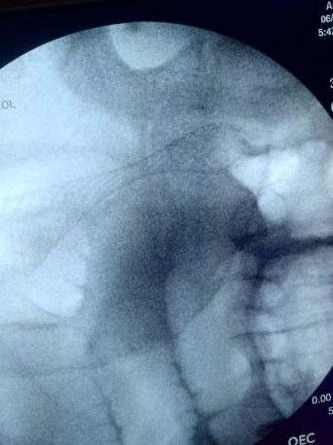

Colonic stent placement was performed under general anesthesia. The patient was placed in the left lateral decubitus position and a double channel therapeutic gastroscope (Olympus America) was passed into the rectum until an area of complete colonic obstruction was reached in the sigmoid colon. The fluoroscopy was also used in this procedure. The luminal obstruction was so severe we have to use ERCP cannula and 0.025 in angled visiglide wire (Olympus America) under fluoroscopy to access the obstructed proximal part of the dilated colon through the tumor. Then a 25 mm x 90 mm Boston Scientific colonic stent was deployed (Figure5) successfully, and stool was visualized coming through the stent from the obstructed part of the colon (Figure 6). A follow-up x-ray of the abdomen was used to confirm there was no adverse event like perforation (free air under the diaphragm).

Figure 5. Initial stent deployment with passage of stool

Figure 5